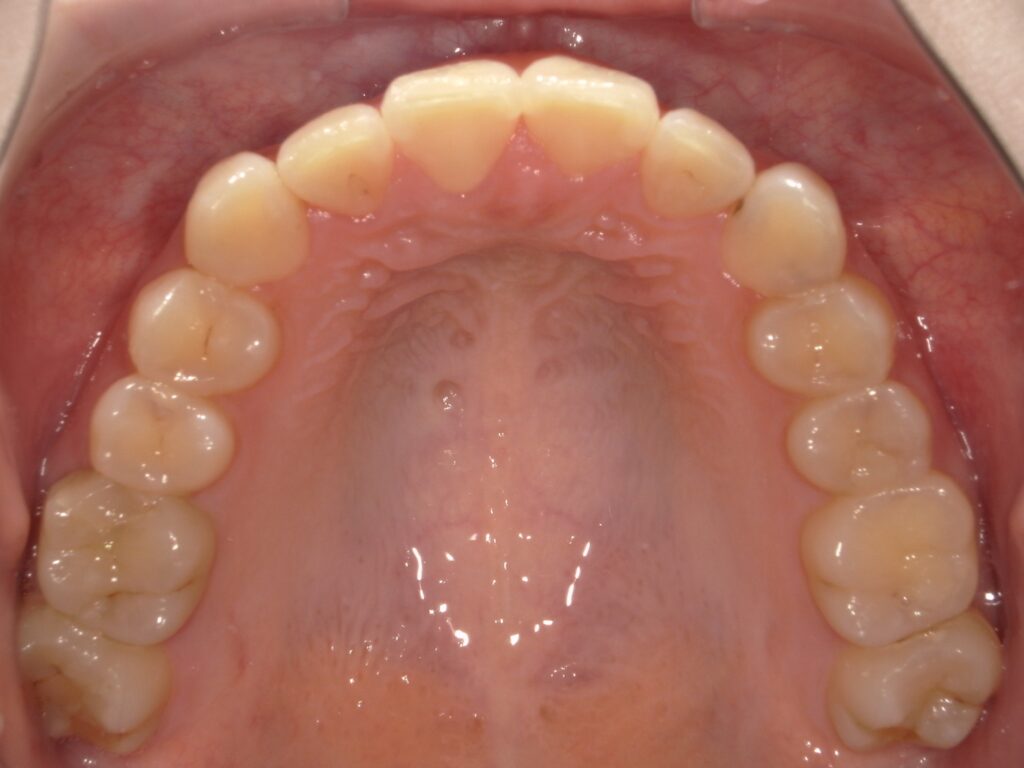

Before

After

口元の改善 / Eライン

- 20代女性

- 主訴:前歯を下げたい

- 矯正方法:インビザラインの非抜歯矯正

- 治療期間:13ヶ月

- 治療費:715,000円

- その他ご要望:歯を抜かずに口元をできる限り下げたいとのご希望。

- 詳しくはこちら

ご相談内容 前歯が出ていることが気になると20代女性からのご相談 現状と治療方針 上の前歯が出ており、口元の突出感が見られます。歯を抜くことに抵抗がある患者様だったため、奥歯をさらに後ろに下げることのできる遠心移動という方法を用いて、歯を抜かずに口元を下げる治療計画を作成しました。 治療結果 非抜歯で前歯を13ヶ月で下げることができ、横から見た際の口元の変化も見られました。 振り返り 今回の患者様は口元が出ていることにコンプレックスを感じていらっしゃり、また、歯を抜くことに抵抗もあったため、「歯を抜かずにEラインを改善する」ことができる矯正歯科を探しておられました。歯を抜かなくても口元の印象が変わったことに大変喜ばれていました。 リスク・副作用 マウスピースの装着時間を守っていただけないと矯正治療に時間がかかり、場合によっては治療がうまく進まない可能性があります。